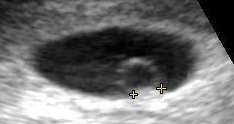

난황낭은 임신 초기 임신낭 내에서 관찰되는 첫 번째 요소로, 보통 임신 3일차에 관찰된다.[1] 난황낭은 배아의 앞쪽(복부)에 위치하며, 배아 바깥쪽의 내배엽으로 덮여 있고, 그 바깥쪽은 상배엽에서 유래된 배아 외 중간엽 층으로 구성된다.[3]

난황낭은 임신 중 임신낭 내에서 처음 관찰되는 요소이며, 일반적으로 임신 3일차에 관찰된다.[1]